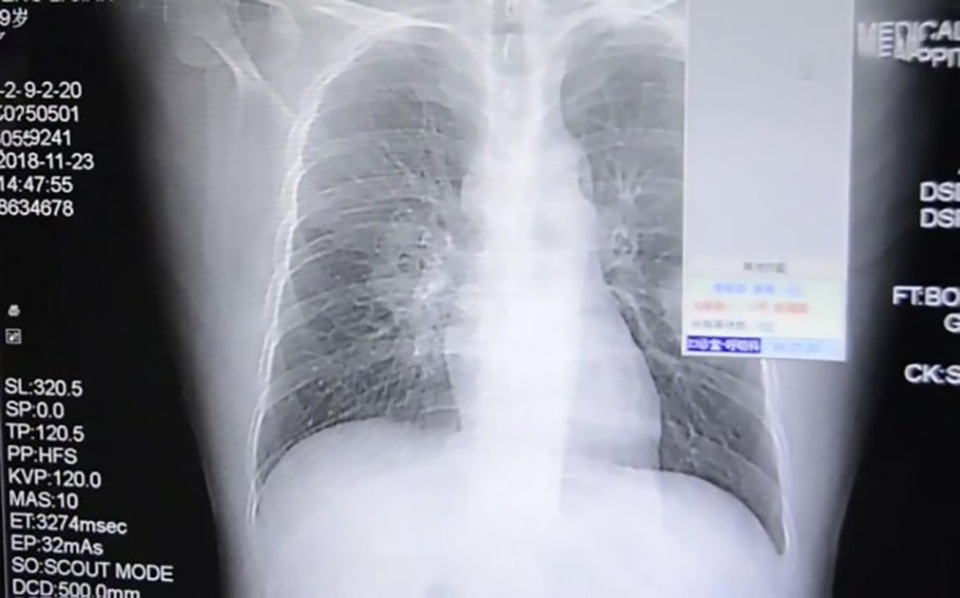

Các bác sĩ nghi ngờ Peng bị viêm phổi, nhưng sau khi sử dụng mọi biện pháp không hiệu quả, các bác sĩ đã tiếp tục làm các xét nhiệm và khẳng định Peng bị nhiễm nấm ở trong phổi.